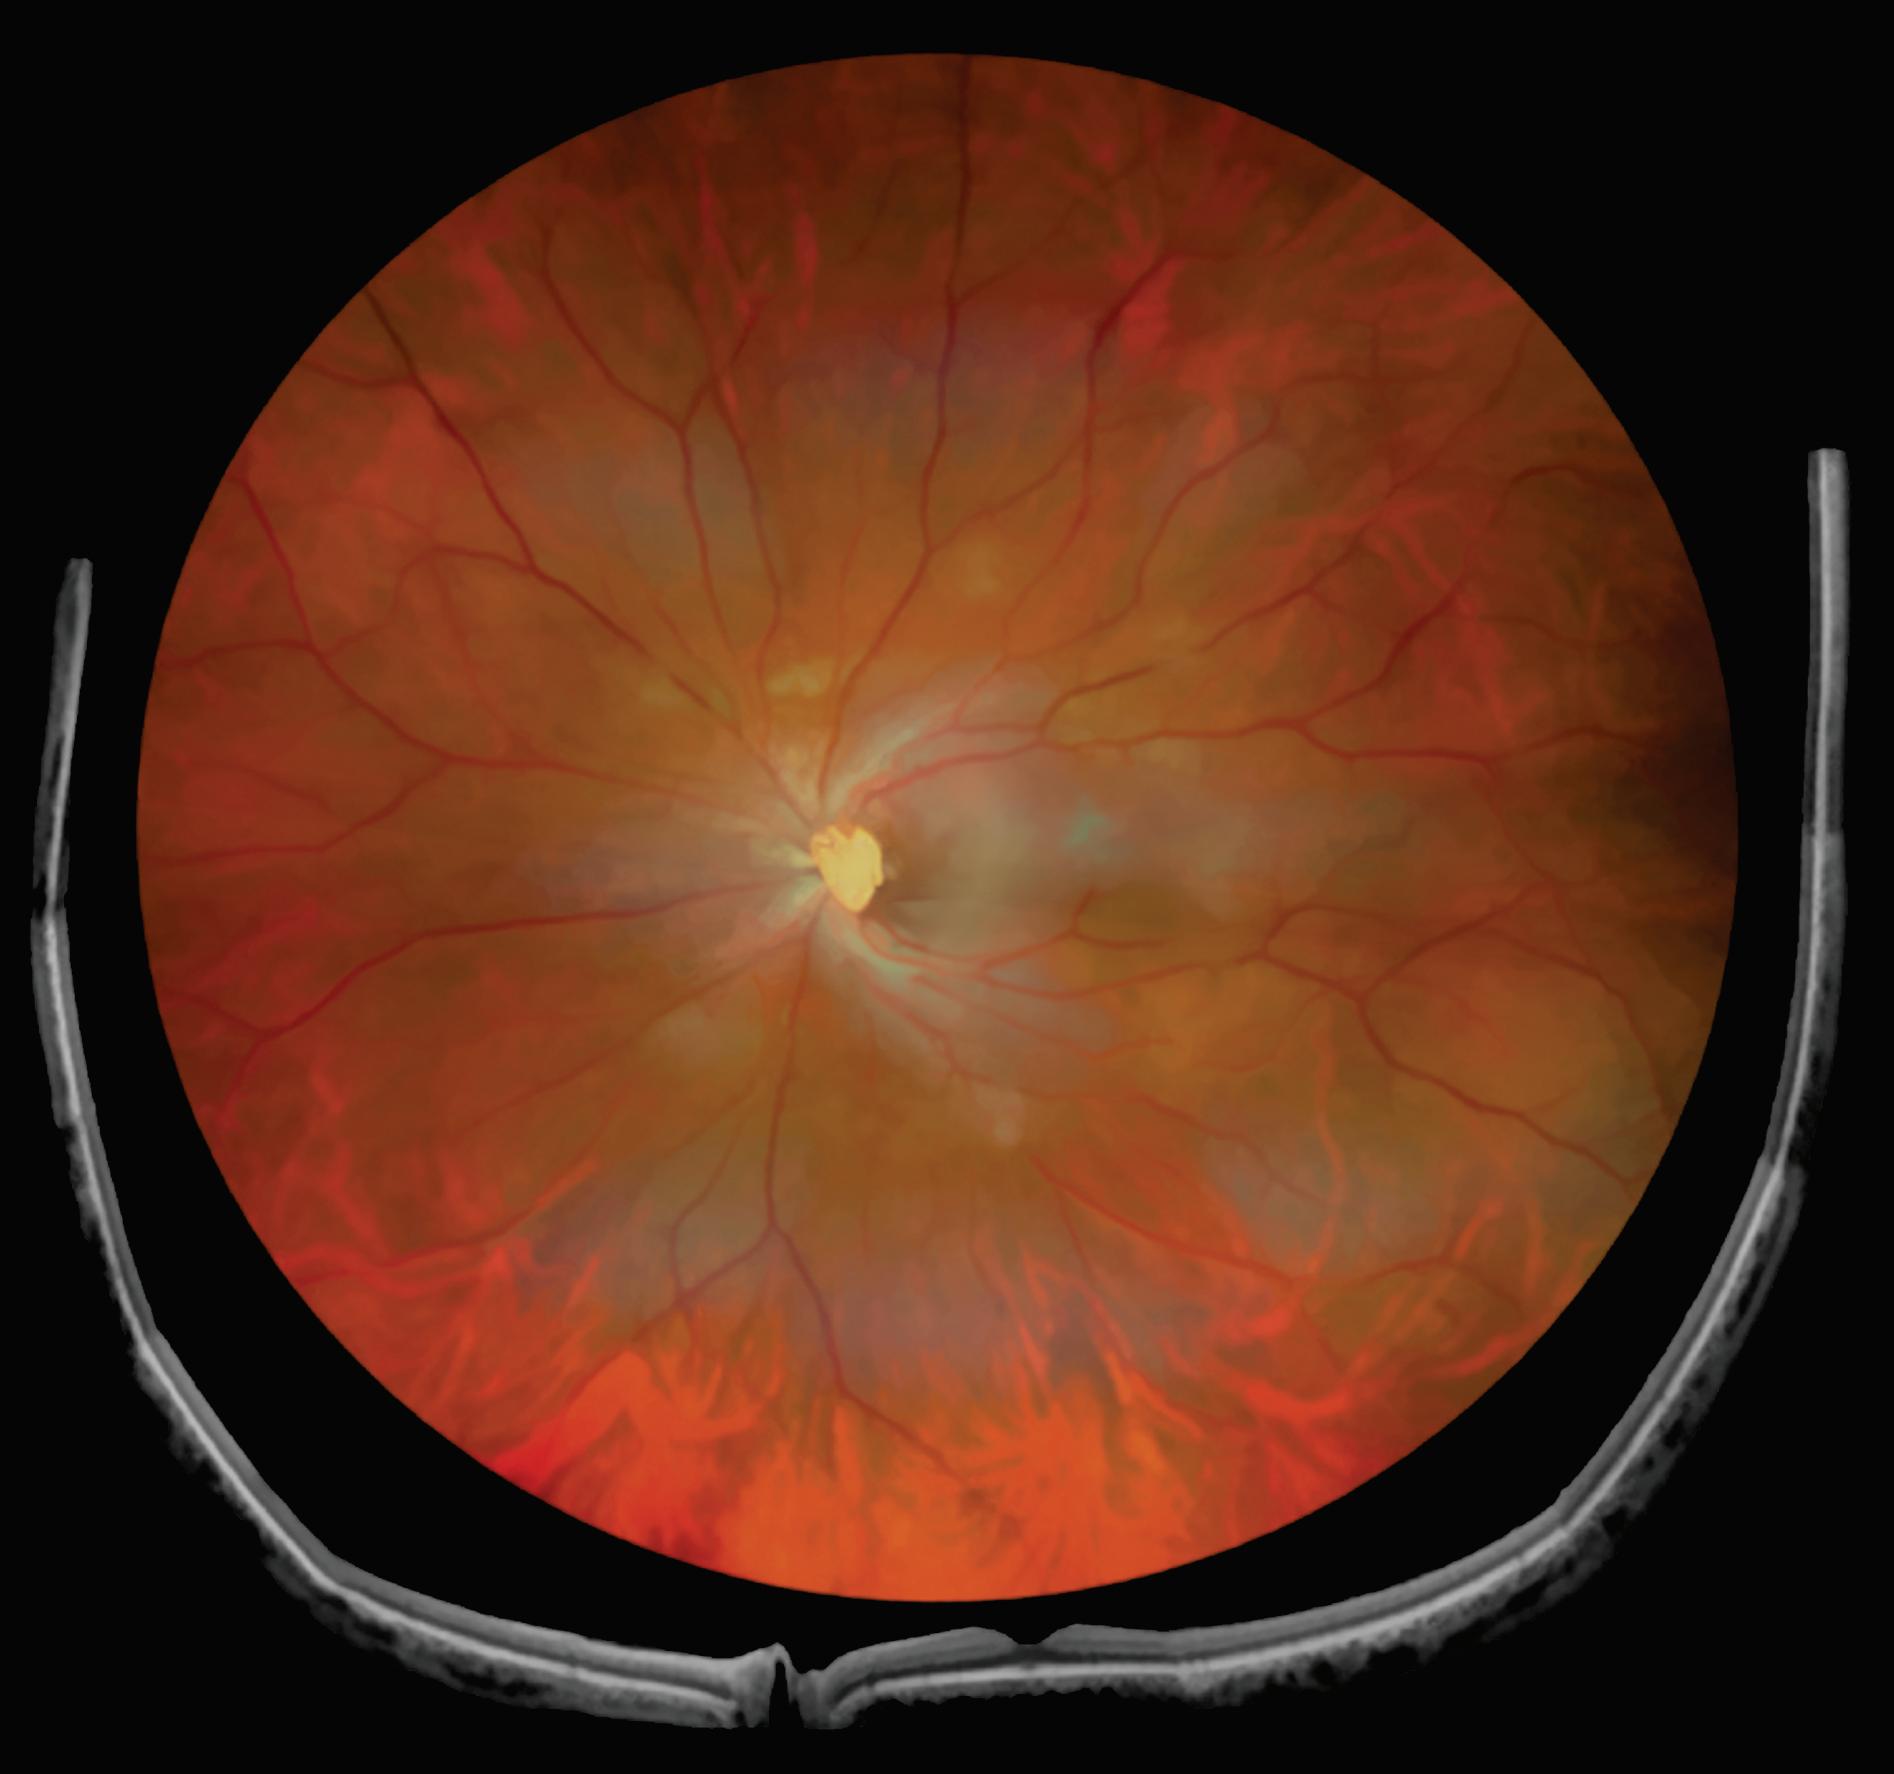

Um exemplo da capacidade da OCT para prever a acuidade visual pós-operatória em olhos com descolamento de retina regmatogênico (RRD) sem mácula está na Figura 1-27.20 Outras áreas da medicina se beneficiam igualmente da técnica da tomografia de coerências ótica . Para citar algumas: dermatologia no diagnóstico de lesões da pele como carcinomas etc. Na cardiologia se usa para obter imagens de alta resolução das artérias coronárias. O método de OCT por endoscopia foi introduzido em 1997 pelo pesquisador James Fujimoto no MIT e outros colaboradores. Finalmente, na indústria de semicondutores na medição não destrutiva das camadas finas dos seus dispositivos. O campo das aplicações do uso da OCT é cada vez mais amplo e se pode afirmar que novos e melhores equipamentos estão por vir.

1-27. Imagens pré-operatórias de tomografia de coerência óptica (oCT). Um círculo com um diâmetro de 2 mm foi posicionado manualmente no centro da superfície foveal da mácula destacada na imagem de oCT. a área macular dentro do círculo foi dividida em três seções: camada interna (superior direita: camada de fibras nervosas e camada de células ganglionares), camada intermediária (inferior direita: camada plexiforme interna e camada nuclear interna) e camada externa (inferior esquerda: camada plexiforme externa e camada nuclear externa). (reproduzida com permissão de https://www.hindawi.com/copyright/.)20